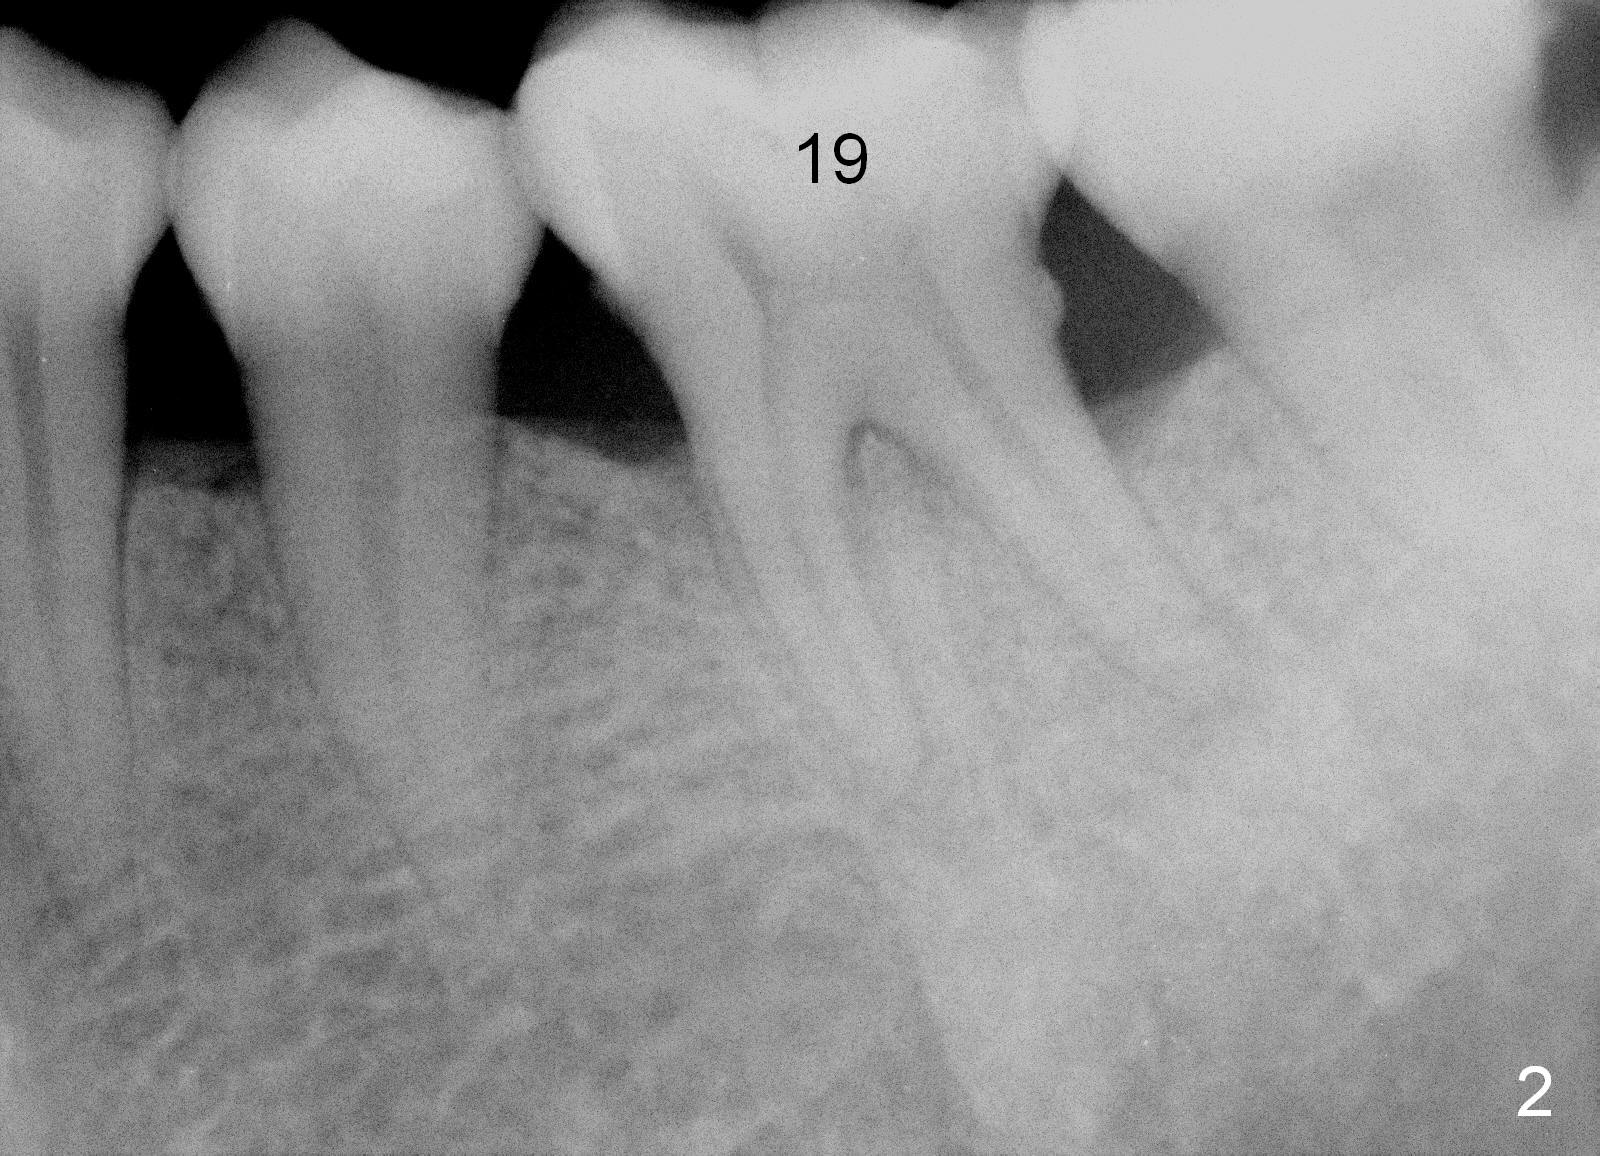

A 43-year-old lady has generalized moderate localized advanced chronic periodontits (Fig.1,2). In spite of 4 quadrant scaling & root planing, the tooth #19 develops 2 perio abscesses (Fig.4 with insertion of 2 guttae perchae); periodontal ligament spaces increases (compare Fig.2,4). It appears that the tooth is non salvageable and should be replaced with an immediate implant (Fig.5). The extraction socket will be treated with Metronidazole. A 2 mm pilot drill is used to start osteotomy in the septum (14 mm deep), followed by reamers until 3.5 mm. A 5x17 mm tap is placed to test stability. If the stability is high, place a 5.3x12 mm SM implant. If insertion torque is too high, use the corresponding drill before re-place the implant. Collagen dressing is placed in the peripheral and deep portion of the sockets, while bone graft in the top portion of the sockets (near implant threads). Use 1 or 2 amalgam carriers to deliver the graft lateral to the implant precisely so that a cover screw does not have to be placed. Next place a cemented abutment. If trajectory of the implant is correct, an abutment as large as 7.8x5(3) mm could be used (pink). Fabricate an immediate provisional. Do not over trim the margin of the provisional so that it can cover the socket completely.